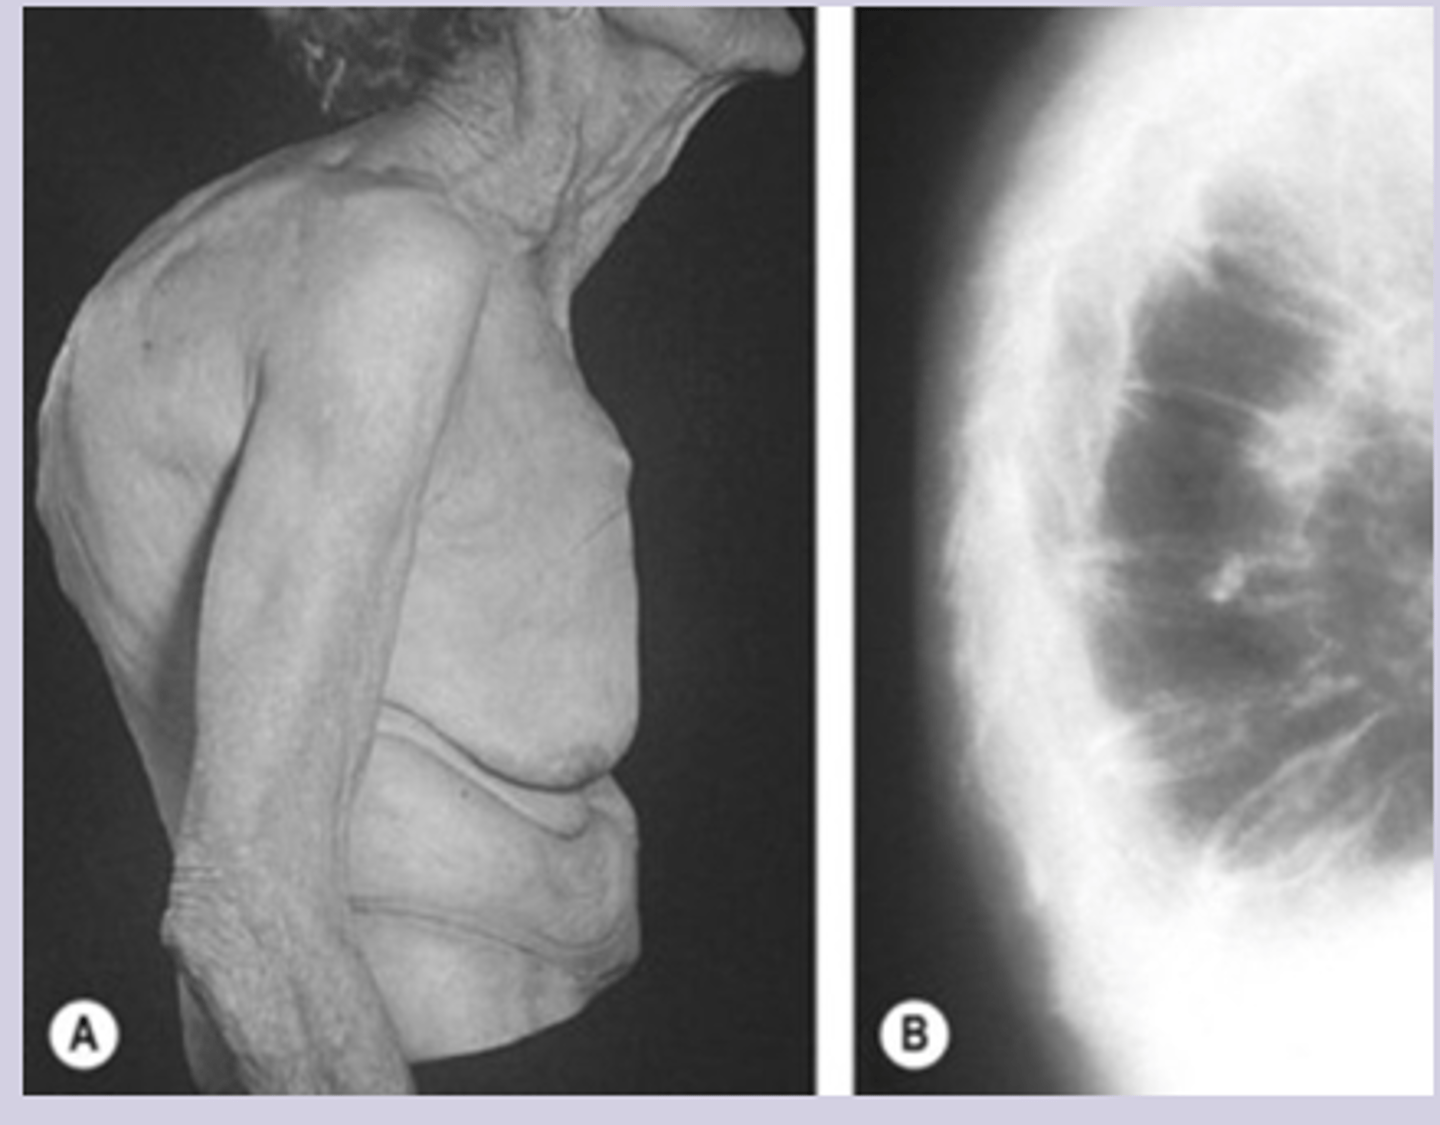

osteoporosis sx

-asymptomatic until fracture

-fragility fracture = fracture from fall from standing height

-loss of height

-kyphosis

-decreased rib to pelvis ratio

Imaging

-used to identify fractures